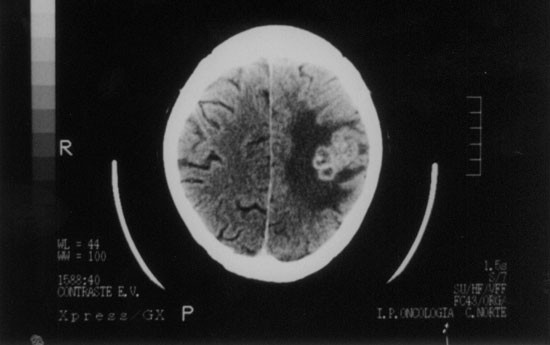

In February 1997, after two severe infectious episodes (Figure 1), he was readmitted with a 2-week history of fever, non-productive cough, exertional dyspnea and weight loss. White blood count was 3.3 × 109/l, the absolute lymphocyte count was 472/mm3 and absolute neutrophil count was above 1.0 × 109/l. A chest X-ray and a CT scan revealed bilateral alveolar infiltrates. Broncho-alveolar lavage (BAL) disclosed Mycobacterium tuberculosis. Drug-sensivity testing did not show criteria of a multidrug-resistant strain. Treatment with isoniazide, rifampin and pyrazinamide was begun. Fever disappeared in a few days and his general condition improved. In May 1997, he presented with headache, dysarthria, papilledema, and signs of a third cranial nerve palsy. CT scan of the brain revealed a large lesion, involving the right temporal lobe (Figure 2). Cultures (blood, sputum, CSF) were negative. Serology tests for toxoplasmosis were negative. Biopsy of the brain lesion disclosed an extensive infiltrate by acid-fast bacilli, later identified by PCR as Mycobacterium tuberculosis. Drug-sensivity testing was not feasible because cultures were inadvertently contaminated. The mass was excised, antituberculous treatment was maintained and immune suppression was continued. Despite neurosurgical sequelae seen on a CT scan of the brain performed 1 month later (Figure 3), neurological recovery was complete. In November 1997 the patient died of septic shock caused by E. coli infection. All throughout the post-transplant period he remained in molecular remission with full donor chimera.